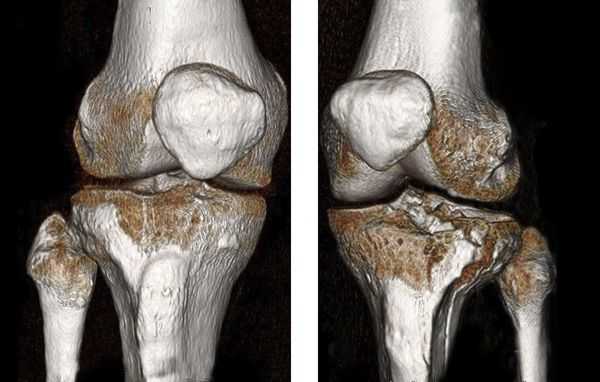

КТ коленных суставов. Внутрисуставной перелом латерального и медиального мыщелков большеберцовой кости

Диагноз перелома мыщелков большеберцовой кости устанавливается врачом-травматологом на основании данных анамнеза, результатов внешнего осмотра и дополнительных исследований. Используются следующие процедуры:

- Объективное обследование. В пользу переломов эпифиза и метафизов большеберцовой кости свидетельствуют резкие боли, усиливающиеся при надавливании на больной мыщелок, типичное нарушение конфигурации пораженной зоны, быстро возникающий значительный гемартроз. Крепитация отломков нехарактерна.

- Рентгенография коленного сустава. Является основным методом инструментальной диагностики. Рентгеновские снимки выполняют в двух проекциях. В абсолютном большинстве случаев это позволят достоверно установить не только факт наличия перелома мыщелков, но и характер смещения отломков.

- Другие визуализационные методики. При неоднозначных результатах рентгенографии пациента направляют на КТ коленного сустава. При подозрении на сопутствующее повреждение мягкотканных структур (связок или менисков) назначают МРТ коленного сустава.